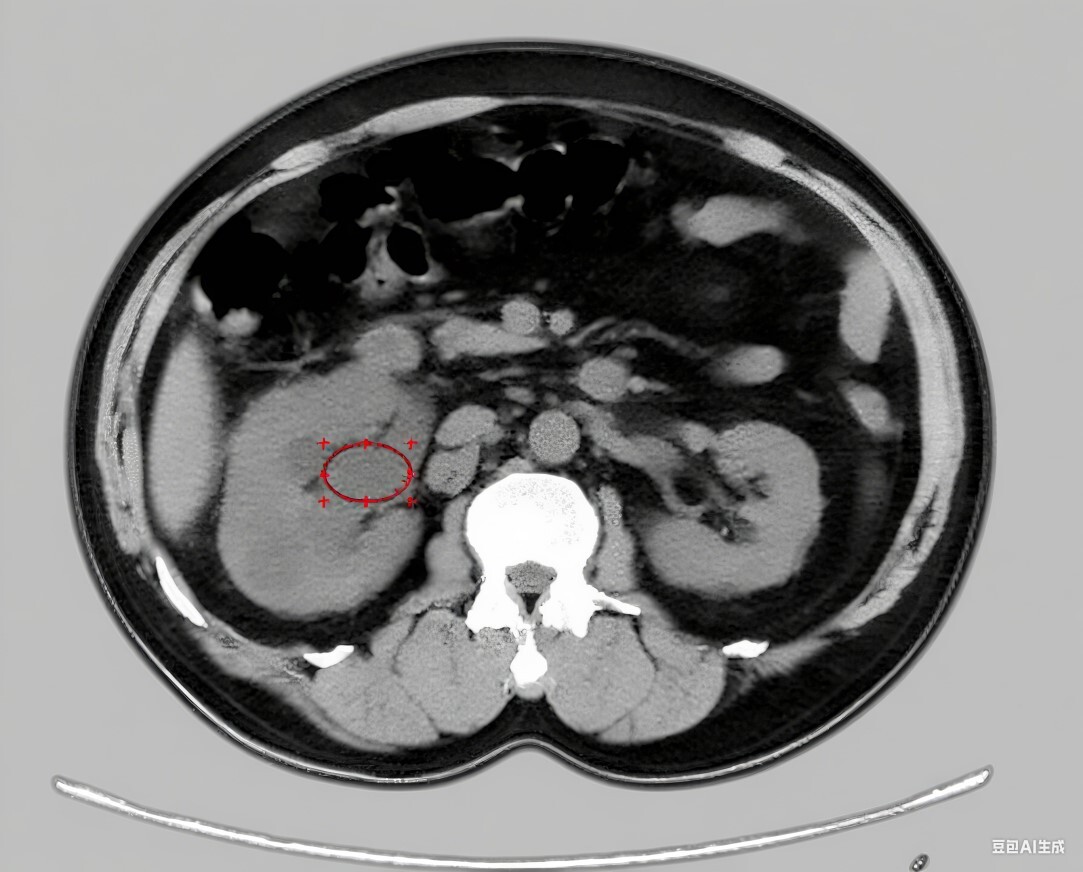

Retrospective studies have explored the association between computed tomography (CT)-derived secondary signs and renal pelvic urine density (RPUD) with postoperative infection after ureteroscopic lithotripsy (URSL). This study evaluated the prognostic value of these indicators in chronic kidney disease (CKD) patients.

Clinical data of patients undergoing URSL for ureteral calculi at two tertiary hospitals from June 2015 to June 2025 were retrospectively collected. Patients were categorized into infection and non-infection groups. Baseline demographics, stone characteristics, RPUD, perinephric fat stranding (PFS), tissue rim sign (TRS), CKD history, and intraoperative variables were compared. Independent predictors were identified via multivariate logistic regression, and a nomogram was constructed.

Postoperative infection occurred in 102 patients (12.6%). The infection group had significantly higher rates of positive preoperative urine culture, diabetes, larger stone diameter, longer operation time, advanced CKD stage, elevated RPUD, and increased incidence of PFS and TRS (all p < 0.05). Multivariate analysis confirmed these variables as independent risk factors. The nomogram demonstrated strong discrimination (C-index = 0.932).

Elevated RPUD combined with positive CT secondary signs (PFS and TRS) is significantly associated with postoperative infection risk in CKD patients undergoing URSL. These easily obtainable non-contrast computed tomography-derived markers offer a novel and practical approach for preoperative risk stratification, enabling individualized preventive strategies and surgical optimization in this high-risk population.